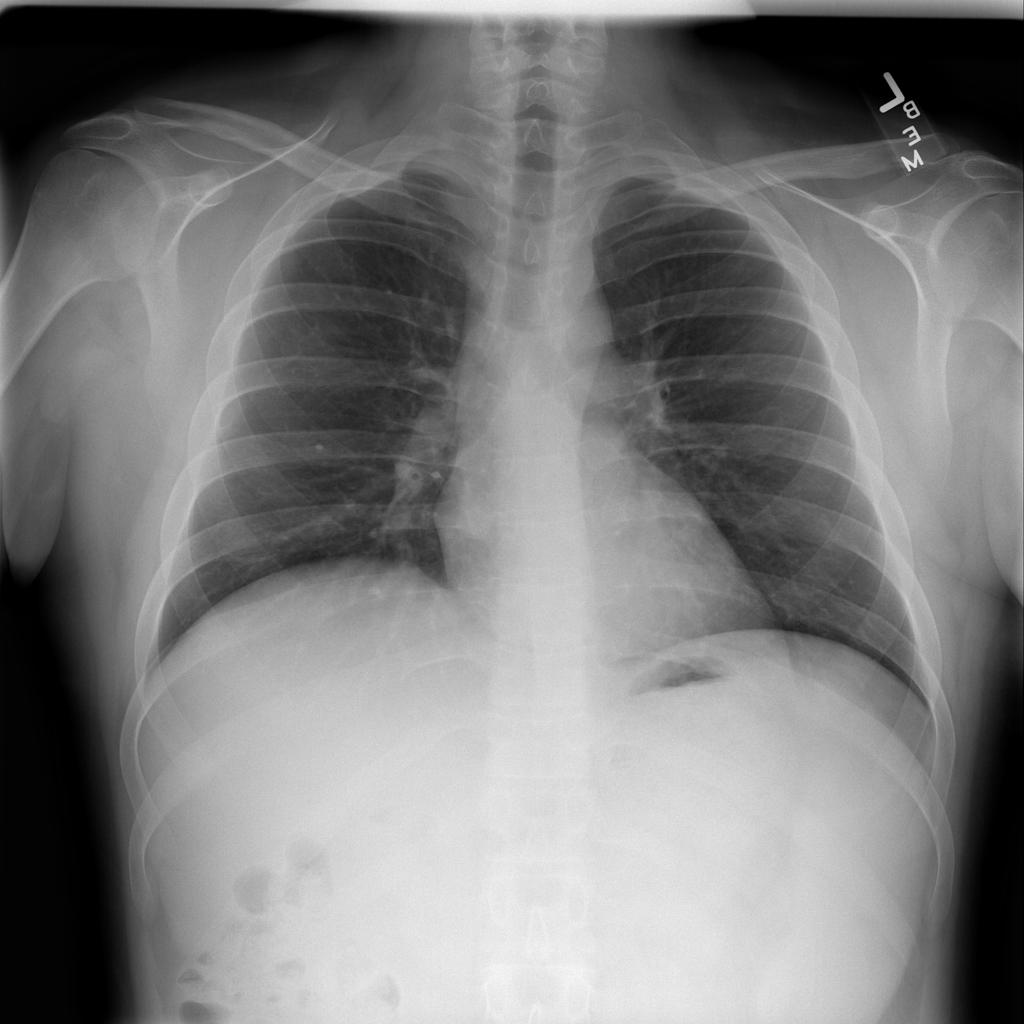

PAT-EBE1 · IMG-019Pneumonia

PAT-EBE1 · IMG-019

AP